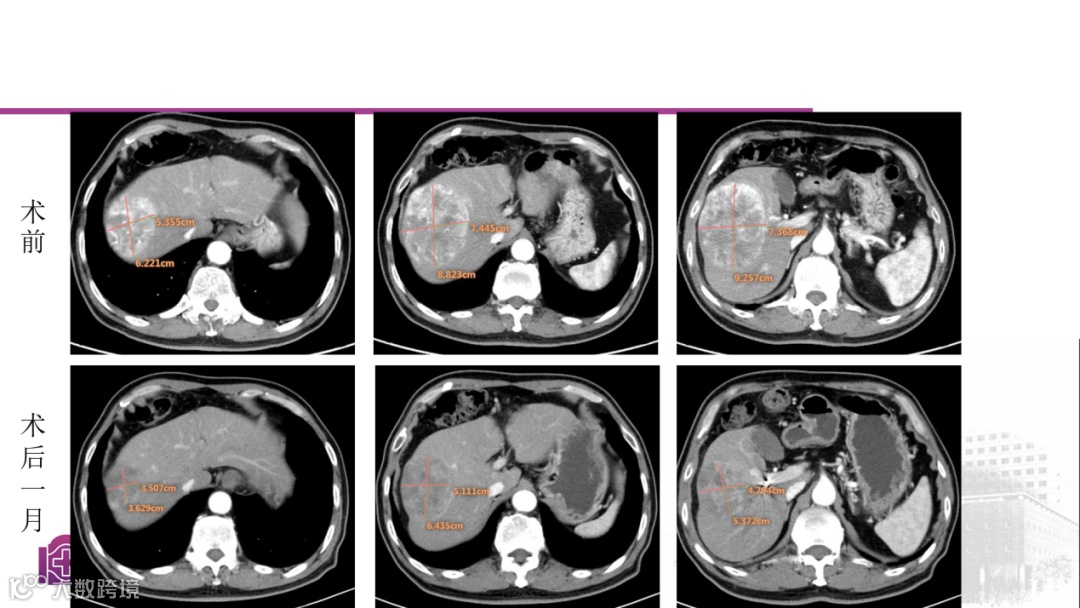

病例二